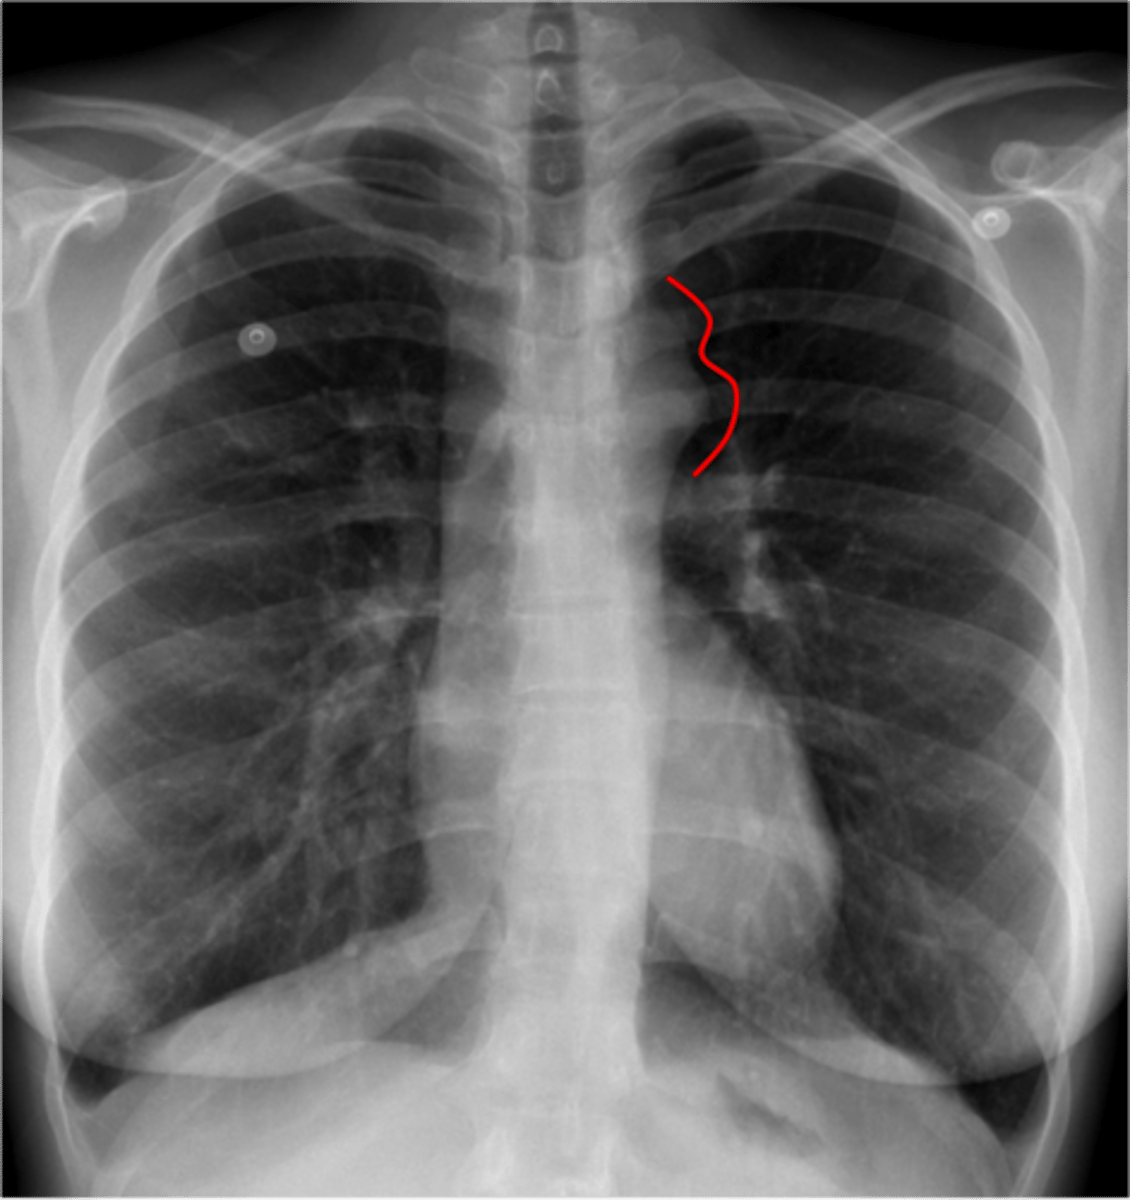

coarctation of aorta

CXR

rib notching

note:

"3 sign" on barium swallow

angiogram gold standard

Tx balloon angioplasty, PGE1